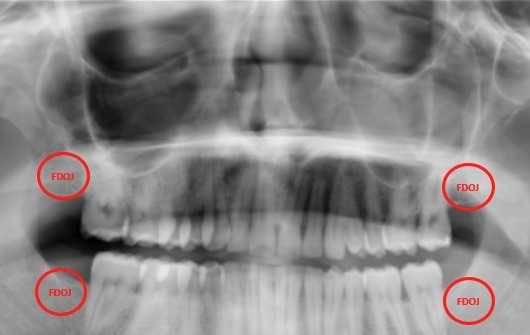

● Chronic fatigue, pain and inflammation have kept me bedridden most days this winter, and I felt the infection in my jaw worsening. A 3D cone beam scan confirmed it.

I’m raising funds for urgent dental surgery by a Biological Dentist in Perth on February 4th to heal a jaw infection that’s been silently damaging my health for years after wisdom teeth removal 20 years ago.